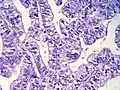

Histopathology

Histopathology is indicated if preoperative imaging and/or gross examination gives a suspicion of gallbladder cancer.[29]

Histopathology of gallbladder carcinoma, with marked nuclear pleomorphism.

Histopathology of gallbladder carcinoma, with marked nuclear pleomorphism. -